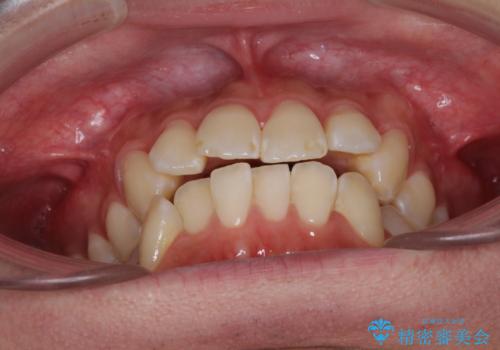

- 前歯のデコボコと若干口元が突出していることを気にして来院された患者様です。

全体的に軽微な叢生が認められ、口元もやや前方に突出していたため、インビザラインでのIPR(歯と歯の間を削る)と歯列全体の後方移動によって歯並びを整えることとしました。

上下ともに歯列の幅が狭かったため、側方に拡大することで前歯のデコボコや突出感を解消するためのスペースを獲得することができました。